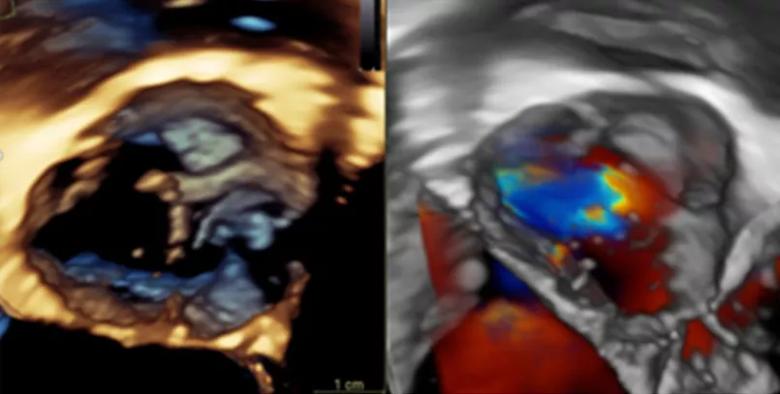

Obtaining the level of detail he sought required three-dimensional (3-D) imaging. Dr. Tretter often uses multiple imaging modalities to comprehensively evaluate their patients, including echocardiography (Figure 1) and often a cardiac MRI, the advantage of which is “a very accurate assessment of heart function and the ability to quantify the extent of leakage or obstruction.” However, he found a CT was best-suited for the detailed 3-D imaging needed to personalize aortic valve surgical planning, which requires detailed measurements to understand the geometry of this complex structure. The newer scanners at Cleveland Clinic produce detailed 3-D images—four-dimensional (4-D) if movement is included (Video 1)—with minimal radiation.

Figure 1. Drs. Tretter and Najm use standard echocardiography imaging to assess the aortic valve, including 3-D echocardiography, as shown here. However, this assessment can be limited depending on the patient’s age and body size.Video 1. An example of a 4-D CT reconstruction of a bicuspid aortic valve.